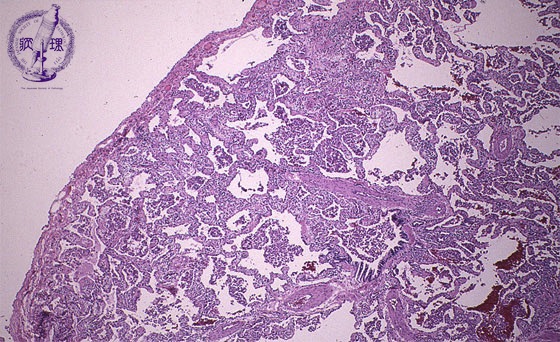

• (12)Interstitial pneumonia(desquamative interstitial pneumonia)

Microscopic view (HE stain, low power view): Alveoli show accumulation of mononuclear macrophages and proliferation of type II pneumocytes and there is a lymphoplasmacytic infiltrate of the interalveolar septum.